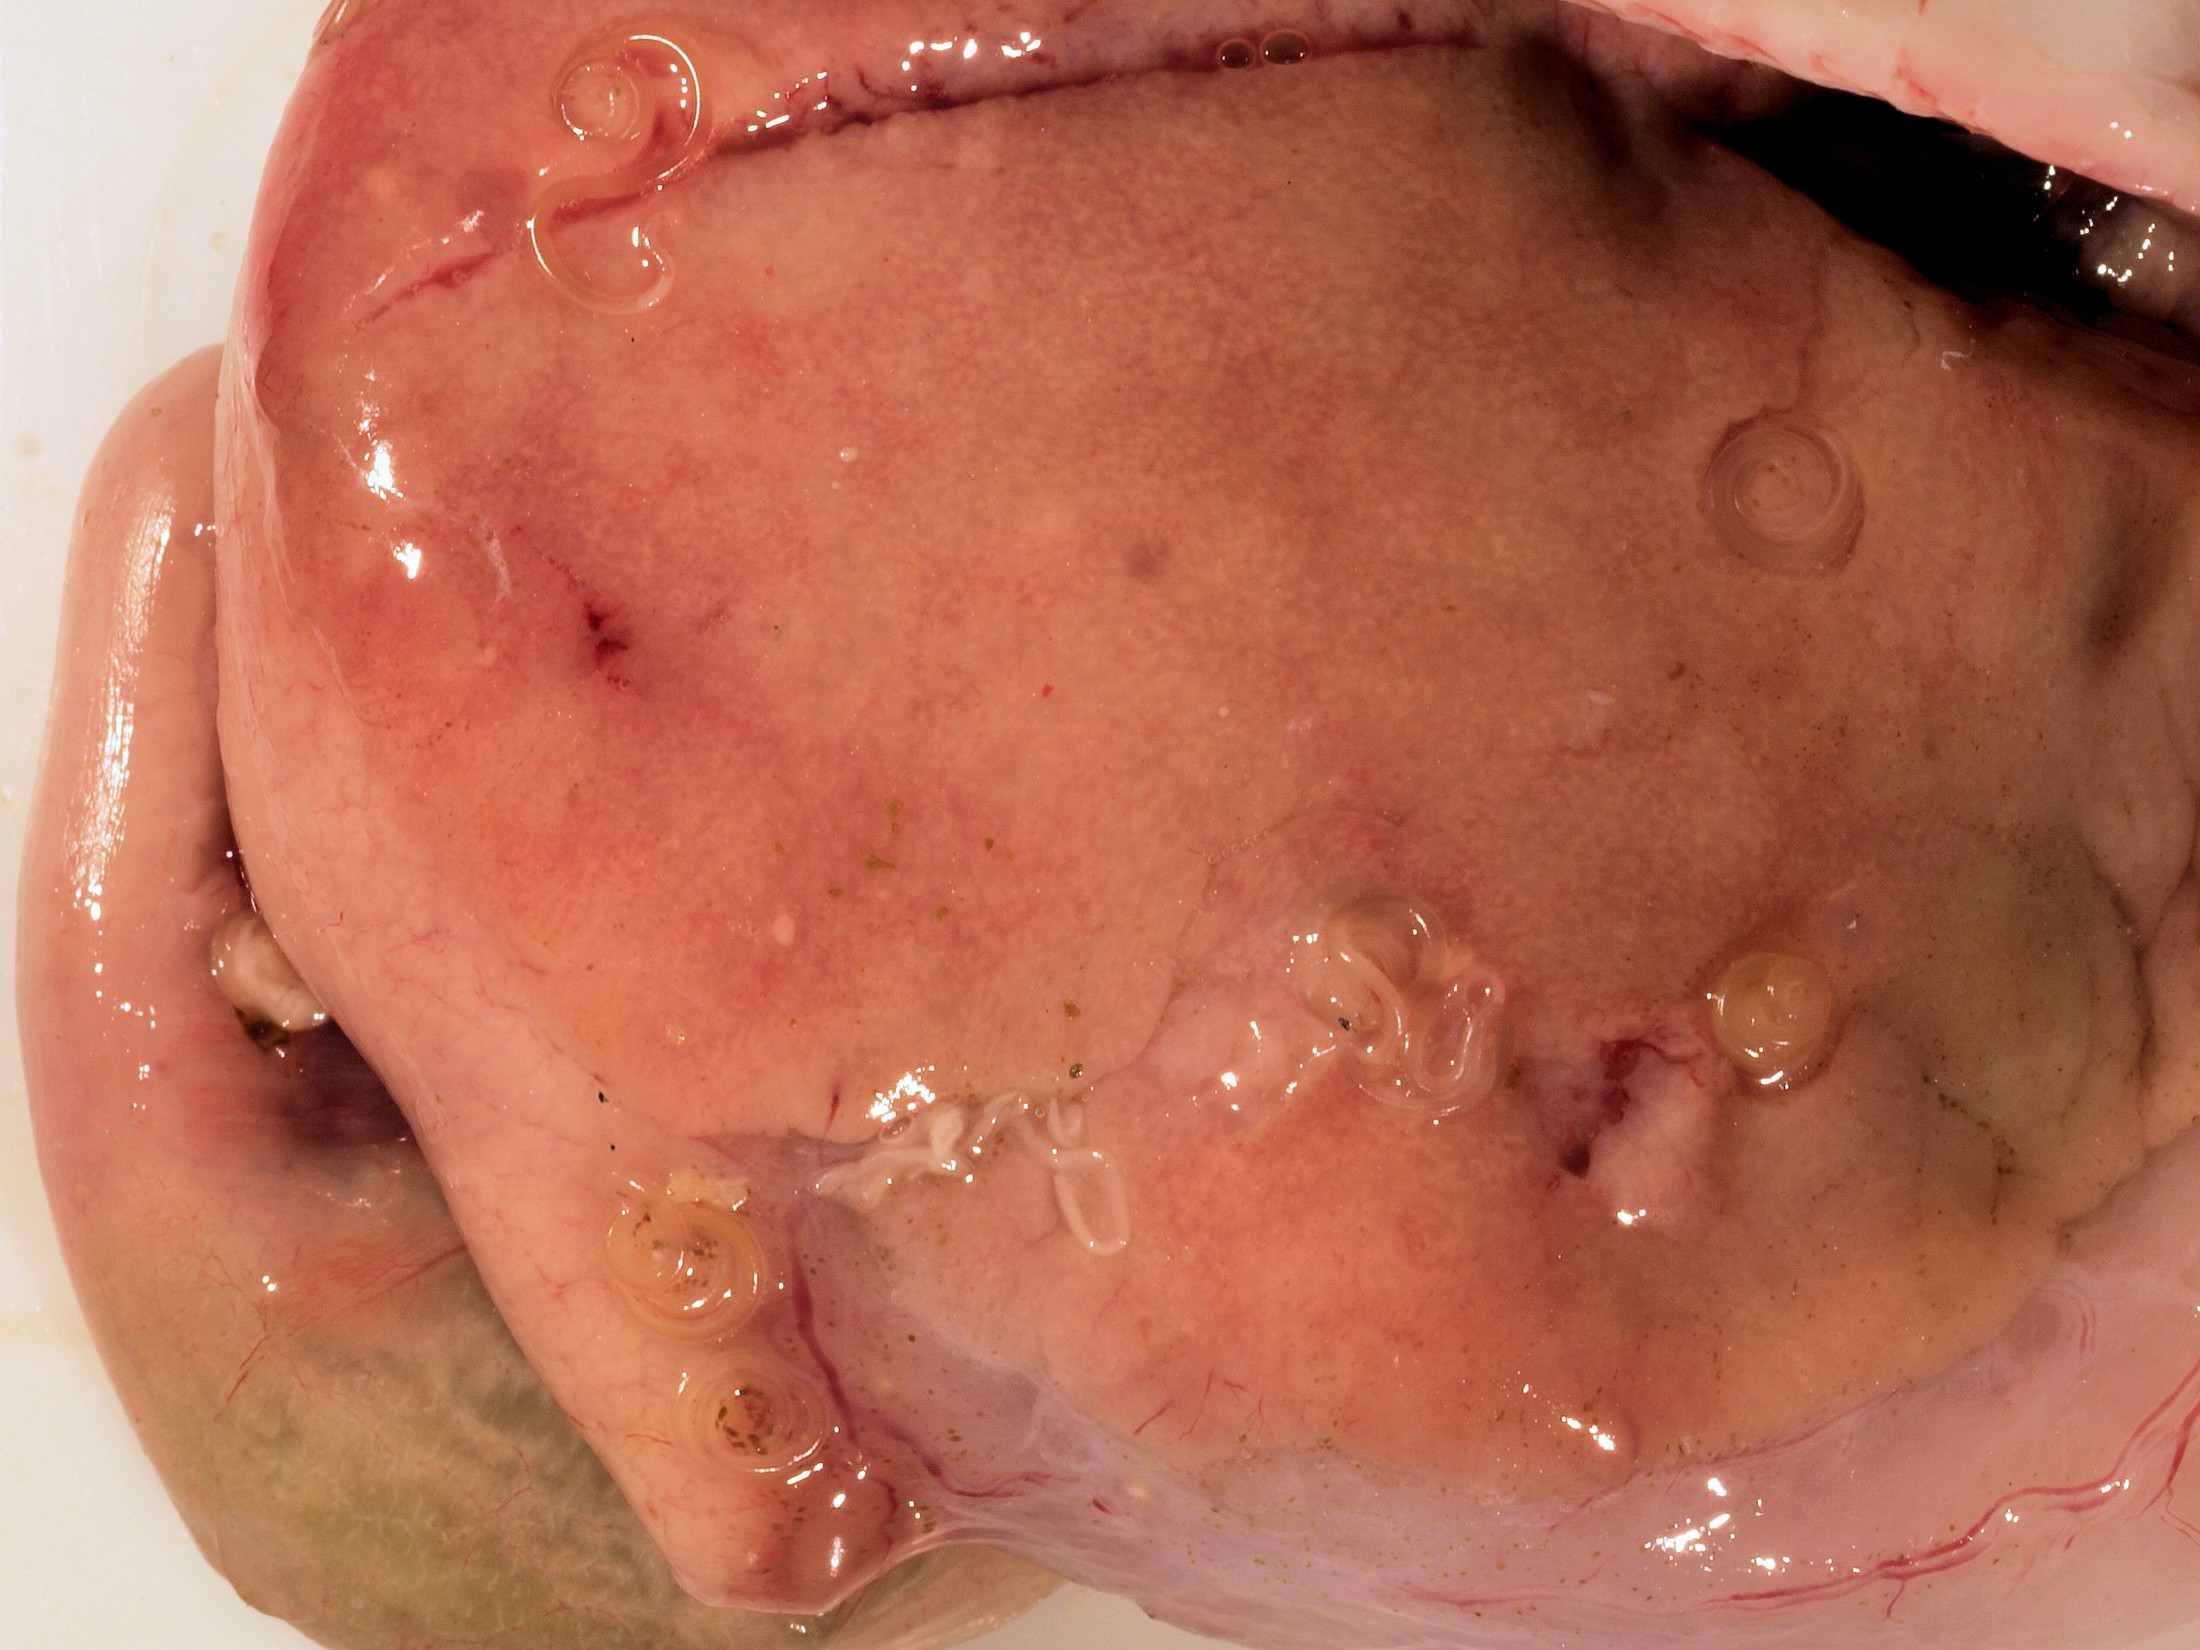

El Gobierno ha declarado por Real decreto, la guerra contra el «anisakis» un parásito que se encuentra exclusivamente en el pescado, cuyas larvas pasan activas al aparato digestivo humano al ingerir pescado crudo o poco cocinado, provocando alteraciones digestivas y reacciones alérgicas.

La anisakiasis humana, en sus vertientes parasitaria y alérgica, es un problema de salud pública cuya incidencia, aun siendo todavía baja, está aumentando en los últimos años, como demuestran diversos estudios del Centro Nacional de Epidemiología y del Comité Científico de la AESA.